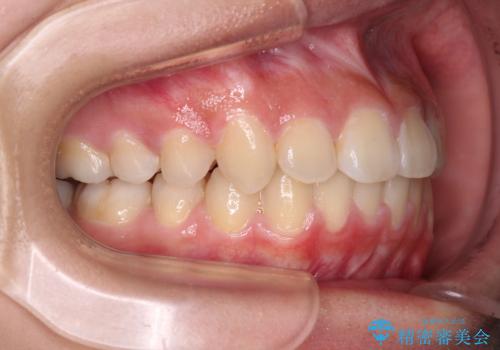

急速拡大装置を用いて上顎骨を側方に拡大し、上顎の叢生を解消するとともに下顎歯列拡大により下顎の叢生も解消することとしました。

急速拡大装置使用直後は著しいスペースが正中に発現するため、ワイヤー矯正を行いますが、今回は治療期間を短くしたいとのことで、上下全体をワイヤー装置にて矯正治療することとしました。

上顎骨を拡大しない場合には、奥歯に咬みにくさが残ったり、下顎前歯の歯肉退縮や口元の突出感などが出たりと、妥協的な仕上がりとなります。